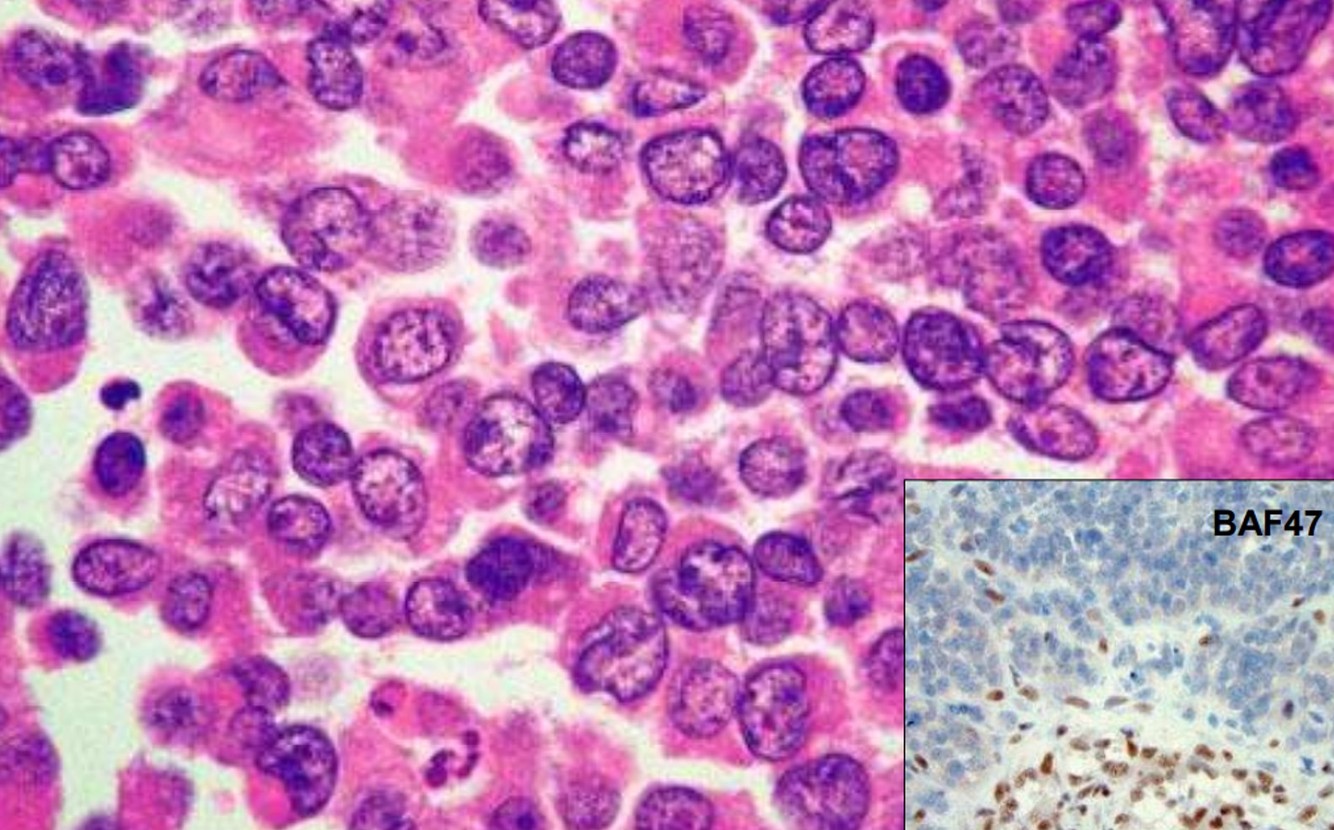

Atypical Teratoid/Rhabdoid tumor

- 2% of pediatric brain tumors

- Highly malignant of young children/infants (up to 5 years of age)

- “Rhabdoid” cells

- Multiple lineage markers (epithelial , muscle)

- Molecular Genetics: >90% of cases show loss/mutations of hSN5/INI1 gene on chromosome 22

- IHC: loss of normal nuclear staining for INI1